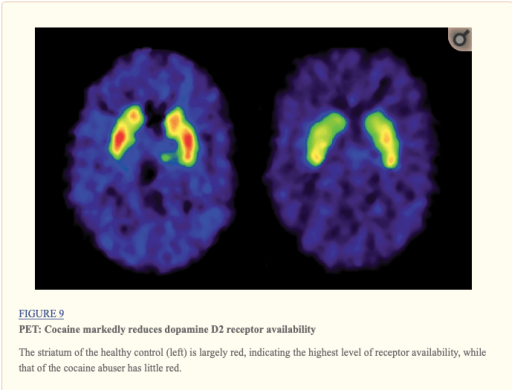

But then they develop tolerance: the amount they used to use no longer causes a release of dopamine. And in the meantime, in response to all the flooding from drug use, their brain has reduced its own dopamine production and sensitivity.

Fowler JS, Volkow ND, Kassed CA, Chang L. Imaging the addicted human brain. Sci Pract Perspect. 2007;3(2):4–16.